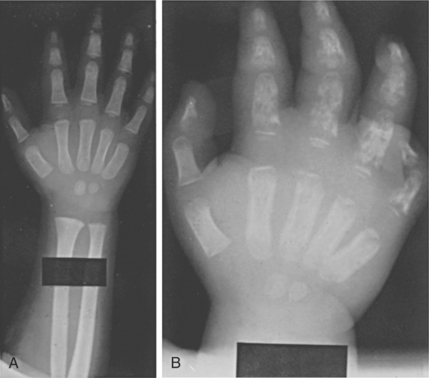

Spinal cord compression is a medical emergency requiring immediate attention. High concentrations of protein are also neuropathic. Amyloidosis (deposits of insoluble fragments of a protein) develops in approximately 10% of people with MM (up to 35% have asymptomatic amyloidosis). These deposits cause tissues to become waxy and immobile and may affect nerves, muscles, and ligaments, especially the carpal tunnel area of the wrist. Carpal tunnel syndrome with pain, numbness, or tingling of the hands and fingers may develop. The association between MM and RA, Sjögren’s syndrome, and other autoimmune diseases has been established, but it is not clear why this occurs.

The diagnosis of MM is determined by clinical factors as well as bone marrow examination. Because other diseases also present with an elevated monoclonal gammopathy, new criteria have been developed by the International Myeloma Working Group to aid in the diagnosis and distinction of these paraprotein diseases in order to provide appropriate treatment.39